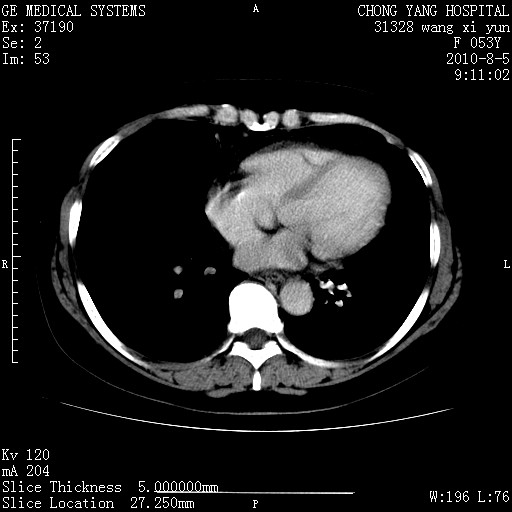

标题: CT28214:F41Y 血尿二十天,建议盆腔平扫加增强。

胆管细胞ca?

1)考虑肝左叶胆管细胞癌。2)脂肪肝。

支持胆管细胞ca。